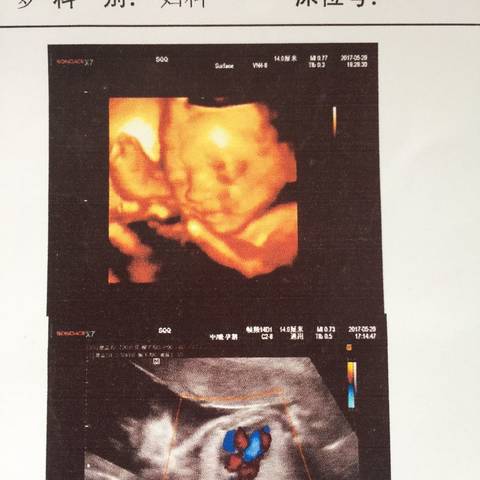

四维确认女宝b超图

四维确认女宝b超图,女宝的四维图 双腿

19周时b超医生说是女宝四维顺利通过,有会看宝妈吗?

四维彩超女宝图片

四维女孩脸图片

确认女宝四维图24周

女宝特征的四维图